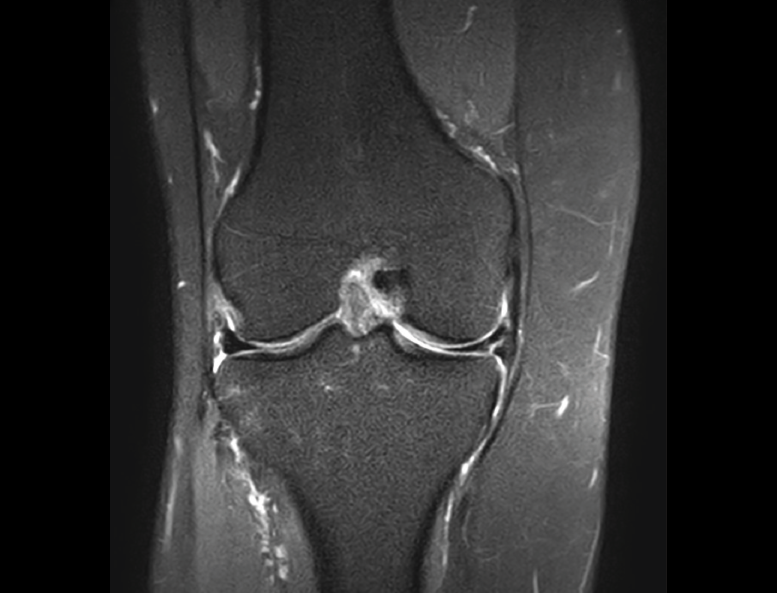

La RM es la técnica de elección en el diagnóstico de la patología meniscal(17)(Figuras 30, 31, 32, 33, 34 y 35).

Figura 32. Corte de secuencia coronal T2 Fat-Sat de resonancia magnética de rodilla: rotura de menisco interno horizontal.

Figura 35. Corte de secuencia coronal y sagital de resonancia magnética de rodilla: rotura en asa de cubo del menisco interno con fragmento desplazado al intercóndilo.

1.2. Ligamentos

Ligamento lateral interno (LLI) y ligamento lateral externo (LLE) (Figuras 36, 37, 38 y 39).

Figura 37. Corte de secuencia coronal T2 Fat-Sat de rodilla: pequeño edema en el LLI, banda medial por esguince del LLI de grado I.

Figura 38. Corte de secuencia coronal T2 Fat-Sat de resonancia magnética de rodilla: edema y pequeña rotura de fibras mediales del ligamento lateral interno (LLI). Esguince del LLI de grado II.

Figura 39. Corte de secuencia coronal T2 Fat-Sat de resonancia magnética de rodilla: edema y rotura del ligamento lateral externo de su inserción peroneal con retracción ligamentosa. Esguince de grado III.